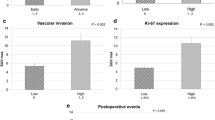

The FDG PET parameters MTV (g/mL) (≤ 8.51, n = 80; >8.51, n = 80) and TLG (bw × cm3) (≤ 29.8, n = 77; >29.8, n = 83) were not significantly associated with DFS, whereas SUVmax and SUVpeak were significantly associated with DFS (p = 0.010 and 0.005, respectively). The FAMT PET parameters SUVmax (g/mL) (≤ 2.8, n = 75; >2.8, n = 85) and SUVpeak (g/mL) (≤ 2.3, n = 85; >2.3, n = 75) were not significantly associated with DFS; however, MTV and TLR were significantly associated with DFS (p = 0.014 and 0.040, respectively). Of the pathological parameters, histological differentiation, INF, TNM stage, and overall stage were significantly associated with DFS (p < 0.05).

The multivariate analysis incorporated INF, regional lymph node metastasis, SUVpeak on FDG PET, and MTV on FAMT PET (Table 3). The results indicated that INF [hazard ratio (HR) = 2.30, p = 0.034] and SUVpeak (HR = 2.45, p = 0.045) were significantly associated with DFS and that lymph node metastasis (HR = 2.57, p = 0.03) and MTV (HR = 3.65, p = 0.004) were significant and independent risk factors for OS.

This study had several limitations. First, this study was not directly focused on cell biomarkers (e.g., Ki-67 immunohistochemistry or LAT1 expression) that are closely associated with tumor cell proliferation, the grade of malignancy, and poor outcomes. Second, the semiquantitative evaluation in this study was dependent on the software used to derive the data. Thus, the thresholds used for PET volumetric parameter calculation were determined automatically, and accuracy would suffer if the thresholds were not correct. Therefore, a further study using a combination of clinical data and pathologic data is highly recommended. Finally, the images used automated tumor delineation based on fixed thresholds, which may have also reduced the accuracy.